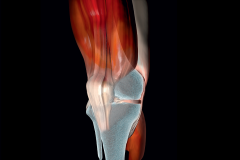

Polecamy też teksty poruszające klasyczne zagadnienia, jednak prezentujące nowe lub rozszerzone podejście do typowych problemów pacjentów. Należą do nich dolegliwości odcinka szyjnego, nerek, zmiany zwyrodnieniowe stawów kolanowych, a także dysfunkcja mięśni dna miednicy.